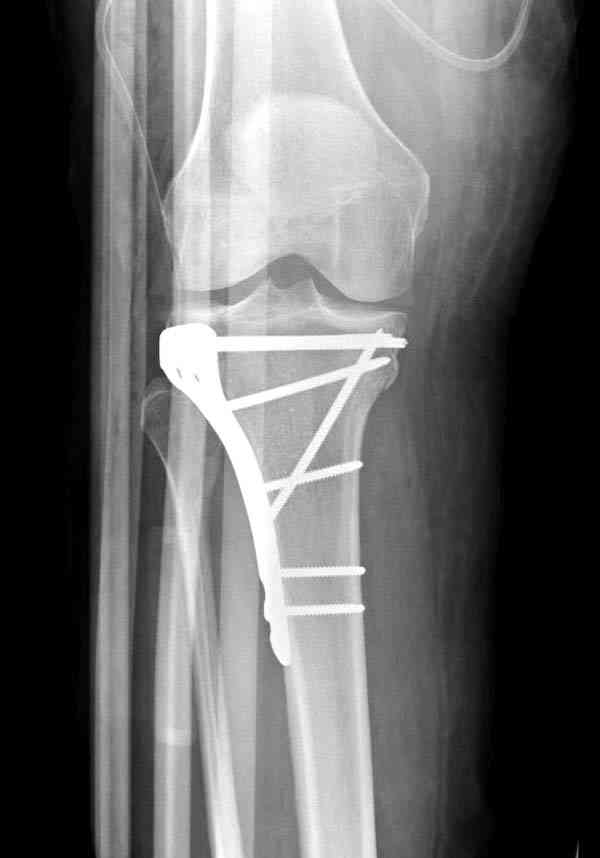

центральная импрессия, а при ипрессии с краевым переломом - после приподнимания импрессии опорная (Butress) пластина, как на снимке.

Из медиального окна можно приподнять латеральную

импрессию. Фиксация тремя параллельными шурупами в

эпифизарной части над импрессией. Создается крыша,

которая предупредит коллапс. На образовавшуюся полость - костная пластика из аутокости или синтетический заменитель. Мы применяем Osteoset в 4-5 мм диаметре таблеточки или иньекционную форму Prodens.